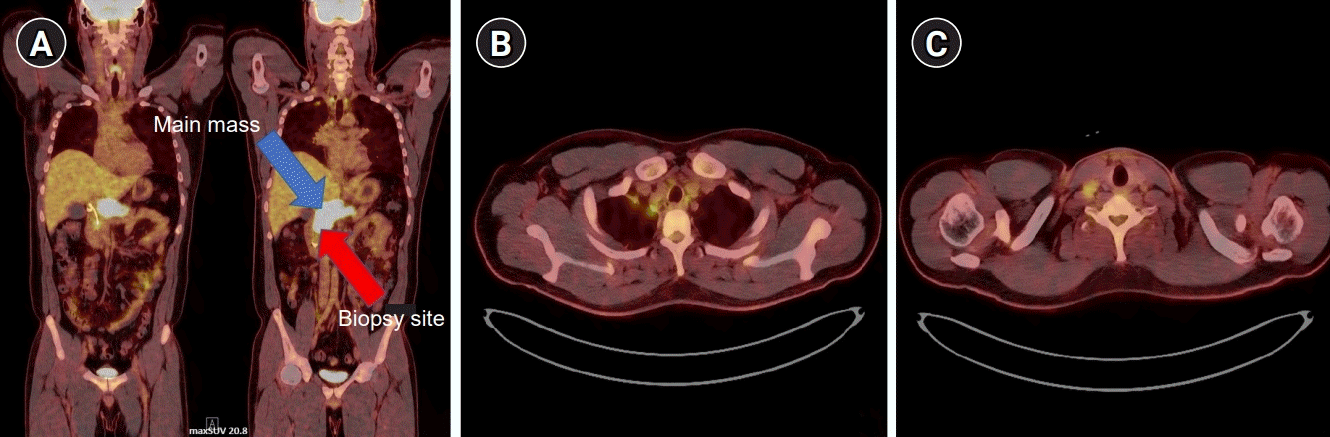

Chest radiography revealed the absence of active lesions. A chest CT revealed no active lesions. Abdominal CT revealed a large mass-like lesion in the pancreatic head and mild dilatation of the common bile duct (CBD). The distal CBD was encased in a mass-like lesion (Fig. 1). Magnetic resonance cholangiopancreatography showed a conglomerated mass with internal necrotic foci and infiltration of the caudate lobe of the liver. Moreover, it shows encasement of the CBD, portal vein, and celiac axis (Fig. 2). The endoscopic retrograde cholangiopancreatography (ERCP) showed a stricture in the mid-CBD. During ERCP, no significant resistance was observed after passing through strictures. Endoscopic ultrasound (EUS)-guided biopsy, brush cytology, and endoscopic retrograde biliary drainage (ERBD) were performed (Fig. 3). Before ERBD insertion, the peak total bilirubin was 6.79 mg/dL. AST and ALT levels were 466 and 801 U/L, respectively. After ERBD insertion, the total bilirubin level decreased to 1.00 mg/dL, and AST and ALT levels decreased to 27 and 65 U/L, respectively, on the 9th day after the procedure. An EUS-guided biopsy confirmed the superficially biopsied bile duct mucosa and benign-looking epithelial cell stripes. The cytological analysis revealed only a limited number of cells.

Positron emission tomography-CT (PET-CT) showed a hypermetabolic mass in the hepatoduodenal ligament with small lymph nodes (LNs) in the aortocaval and retrocaval spaces. Additionally, it showed hypermetabolism of the bilateral palatine tonsils and small hypermetabolic LNs in both neck level II, right supraclavicular space, right upper and lower paratracheal space, and right 2nd internal mammary space (Fig. 4).

Fig. 1.

Liver computed tomography images. (A) Axial and (B) coronal views: a large, mass-like lesion was noted in the pancreatic head (blue arrow).